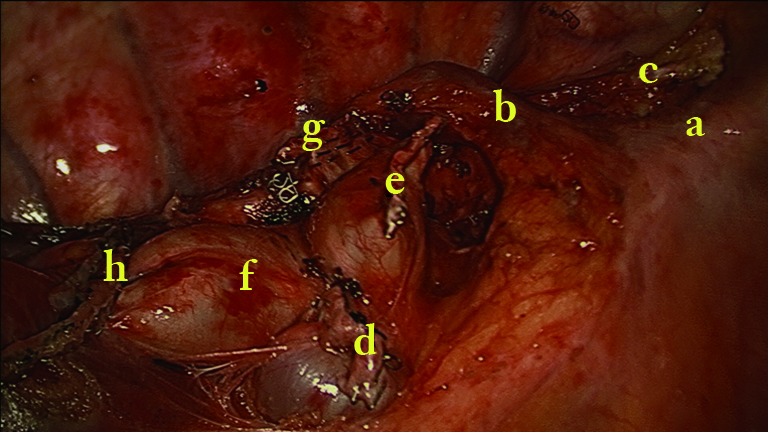

Figure 3.

Uniportal cVATS lobectomy for lung cancer (3).

Move the operating table anteriorly. Systematic lymph node dissection using en bloc excision, instead of systematic sampling, is applied for the removal of 2, 4, 7, 8 and 9 MLNs. We use the same method as in the biportal approach (4). Cut open mediastinal pleura by a “∩” shaped incision for 7th, a “⊿” above azygos vein and “–” beneath azygos vein for 2th and 4th which greatly simplify the en bloc MLNs dissection (Figures 7,8,9).

Figure 7.

Surgical image after lobectomy and systematic lymphadectomy. a, superior vena cava; b, azygos vein; c, vagus nerve; d, stump of superior pulmonary vein; e, stump of truncus anterior; f, the pulmonary artery for middle and lower lobe; g, stump of right upper bronchus; h, the incisal margin of the fissure.